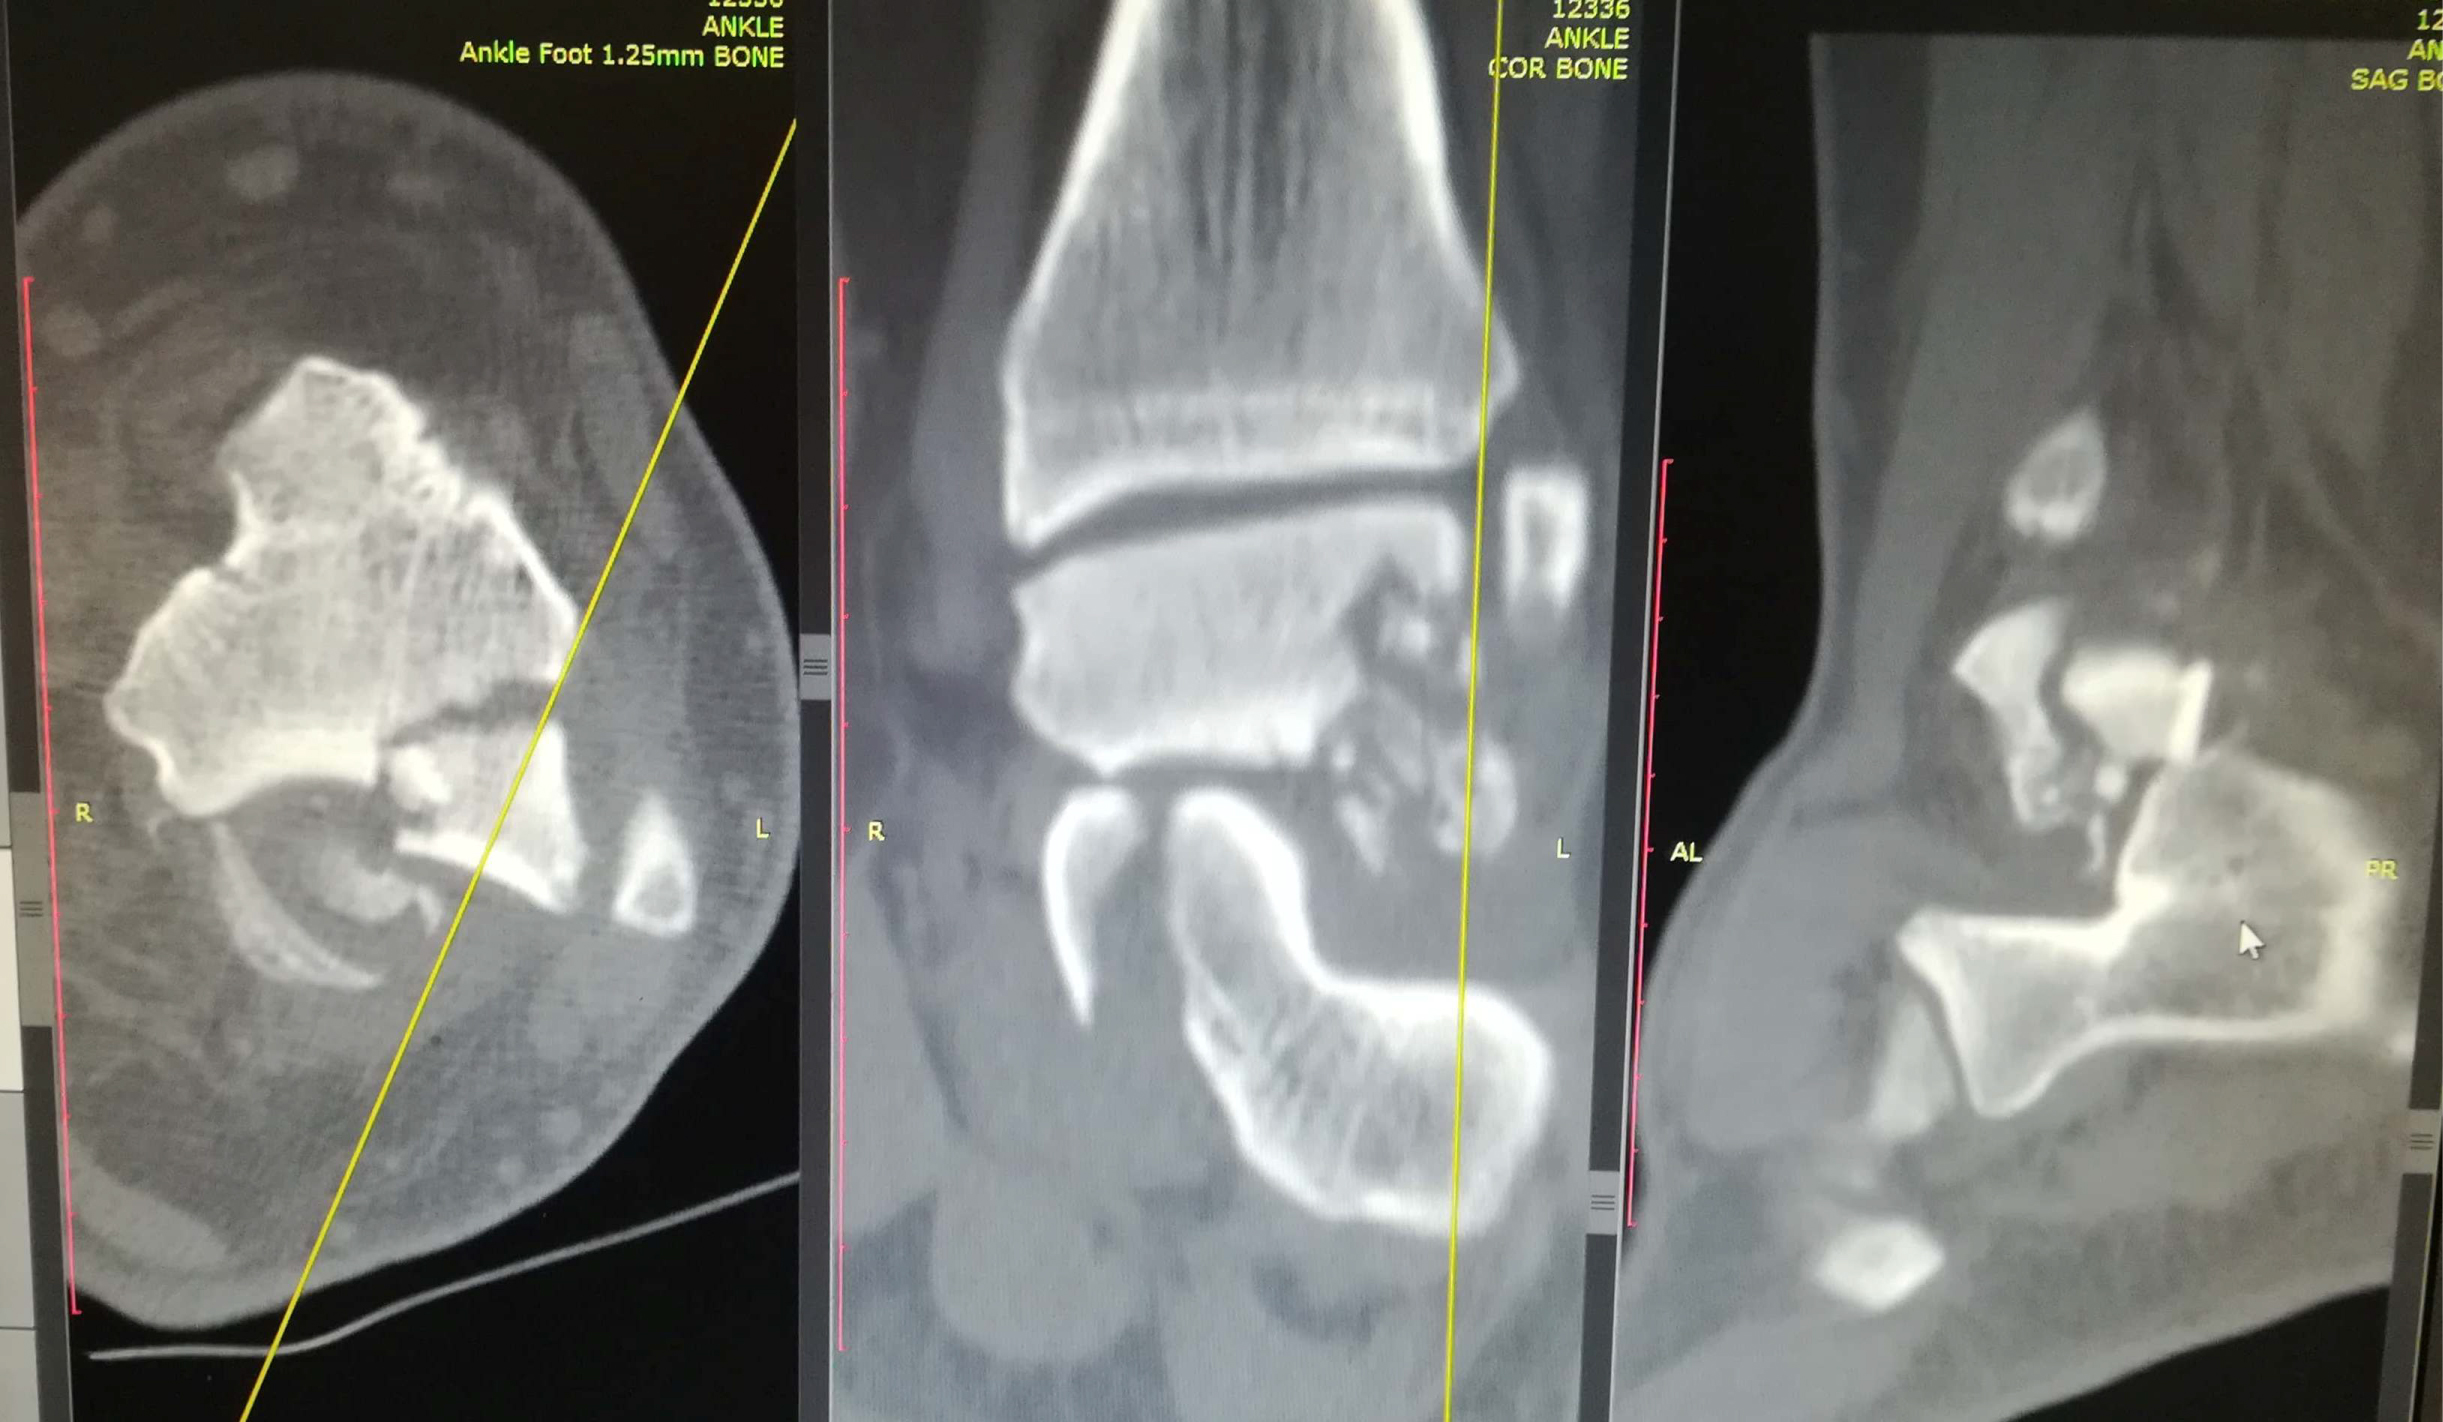

Anteroposterior, mortise and true lateral views of the left foot and ankle radiographs were obtained (Figure 1 and Figure 2). A displaced lateral talar body fracture and subtalar joint disruption, as well as a tilt of the tibiotalar joint, were revealed from the plain radiographs. Osteochondral defect on the medial side of the dome of the talus, due to an old ankle injury, sustained few years ago, was also visible. CT scan of the left foot confirmed a displaced lateral talar body fracture along with a displaced sustentaculum tali fracture (Figure 3, Figure 4 and Figure 5).

Figure 3: Ankle CT scan showing lateral talar body fracture with subtalar subluxation. View Figure 3

Figure 4: Ankle CT scan showing sustentaculum tali fracture with gross displacement. View Figure 4

Figure 5: Ankle CT scan showing lateral talar process fracture with comminution. View Figure 5